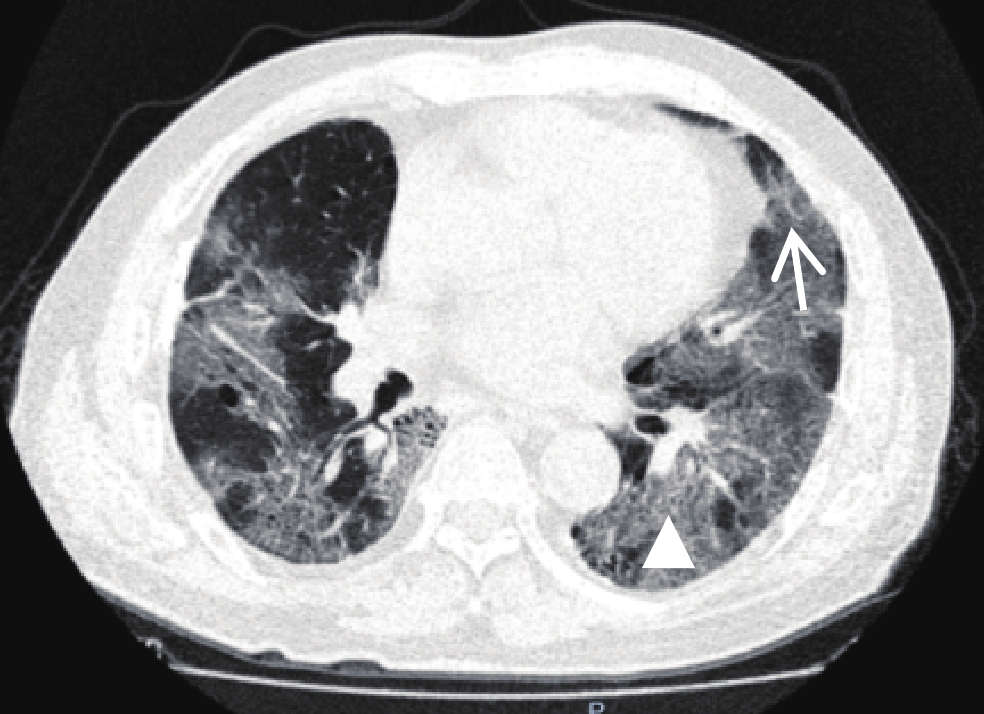

Abstract: Objective: This study aimed to analyze imaging and clinical data of patients with severe and critical coronavirus disease 2019 (COVID-19) with different prognoses and provide help for clinical decision-making. Method: Clinical data and chest imaging computed tomography (CT) of patients with severe and critical COVID-19 were collected. Clinical data included: blood routine indexes, C-reactive protein, procalcitonin (PCT), the indexes of liver and kidney function, D-Dimer, myocardial enzyme, B-type amino terminal natriuretic peptide (LNTP), and whether there was any underlying medical history. The chest CT images and various indexes of patients with different prognoses of COVID-19 were compared. The relevant indicators with significant differences between the two groups were analyzed using binary logistic regression. Results: A total of 118 patients were enrolled, including 68 in the death group and 50 in the survival group. The age of the death group was longer, and the proportion of sputum and poor tolerance was higher than that of the survival group. Compared with the survival group, in the death group, there was a higher abnormal proportion of leukocyte count (WBC), neutrophil absolute value, monocyte absolute value, red blood cell count (RBC), hemoglobin, erythrocyte ratio, abnormal glomerular filtration rate, PCT, D-Dimer, creatine kinase isoenzyme (CK), troponin (TNI), LNTP. Compared with the survival group, WBC, NEUT and percentage, neutrophil/lymphocyte ratio, erythrocyte volume distribution width, erythrocyte volume distribution width standard deviation, PCT, D-Dimer, CK, CK-MB, myoglobin (MYO), TNI and LNTP were significantly increased in the death group, while the lymphocyte percentage, monocyte percentage, mean RBC hemoglobin concentration (MCHC), and glomerular filtration rate were significantly lower. Compared with the survival group, there was no significant difference in the imaging signs of COVID-19 infection in the death group, but the scope of initial chest CT lesions was larger, with more than 50%. In the survival group, more CT lesions were located in the periphery of the lung and subpleura, while in the death group, more lesions showed progression or aggravation. Age, RBC, glomerular filtration rate, CK-MB, MYO, and LNTP were the main factors that suggested prognostic outcomes. Conclusion: Age, blood routine, liver and kidney function, myocardial function, hemagglutination status, inflammatory reactant index, and lung lesion extent and progression of patients infected with COVID-19 are important factors indicating the severity of the disease and poor prognosis. Abnormal increases in leukocyte and neutrophilic granulocyte, CRP, PCT, D-dimer, and myocardial markers might be the main factors that better predict fatal outcomes in severe and critical patients. Abnormalities in age, RBC, glomerular filtration rate, CK-MB, MYO, and LNTP were the main factors indicating fatal outcomes in severe and critically ill patients. Combined with the comprehensive evaluation of clinical and laboratory examinations, imaging findings and follow-up are indispensable methods to evaluate the severity and prognosis of the disease.